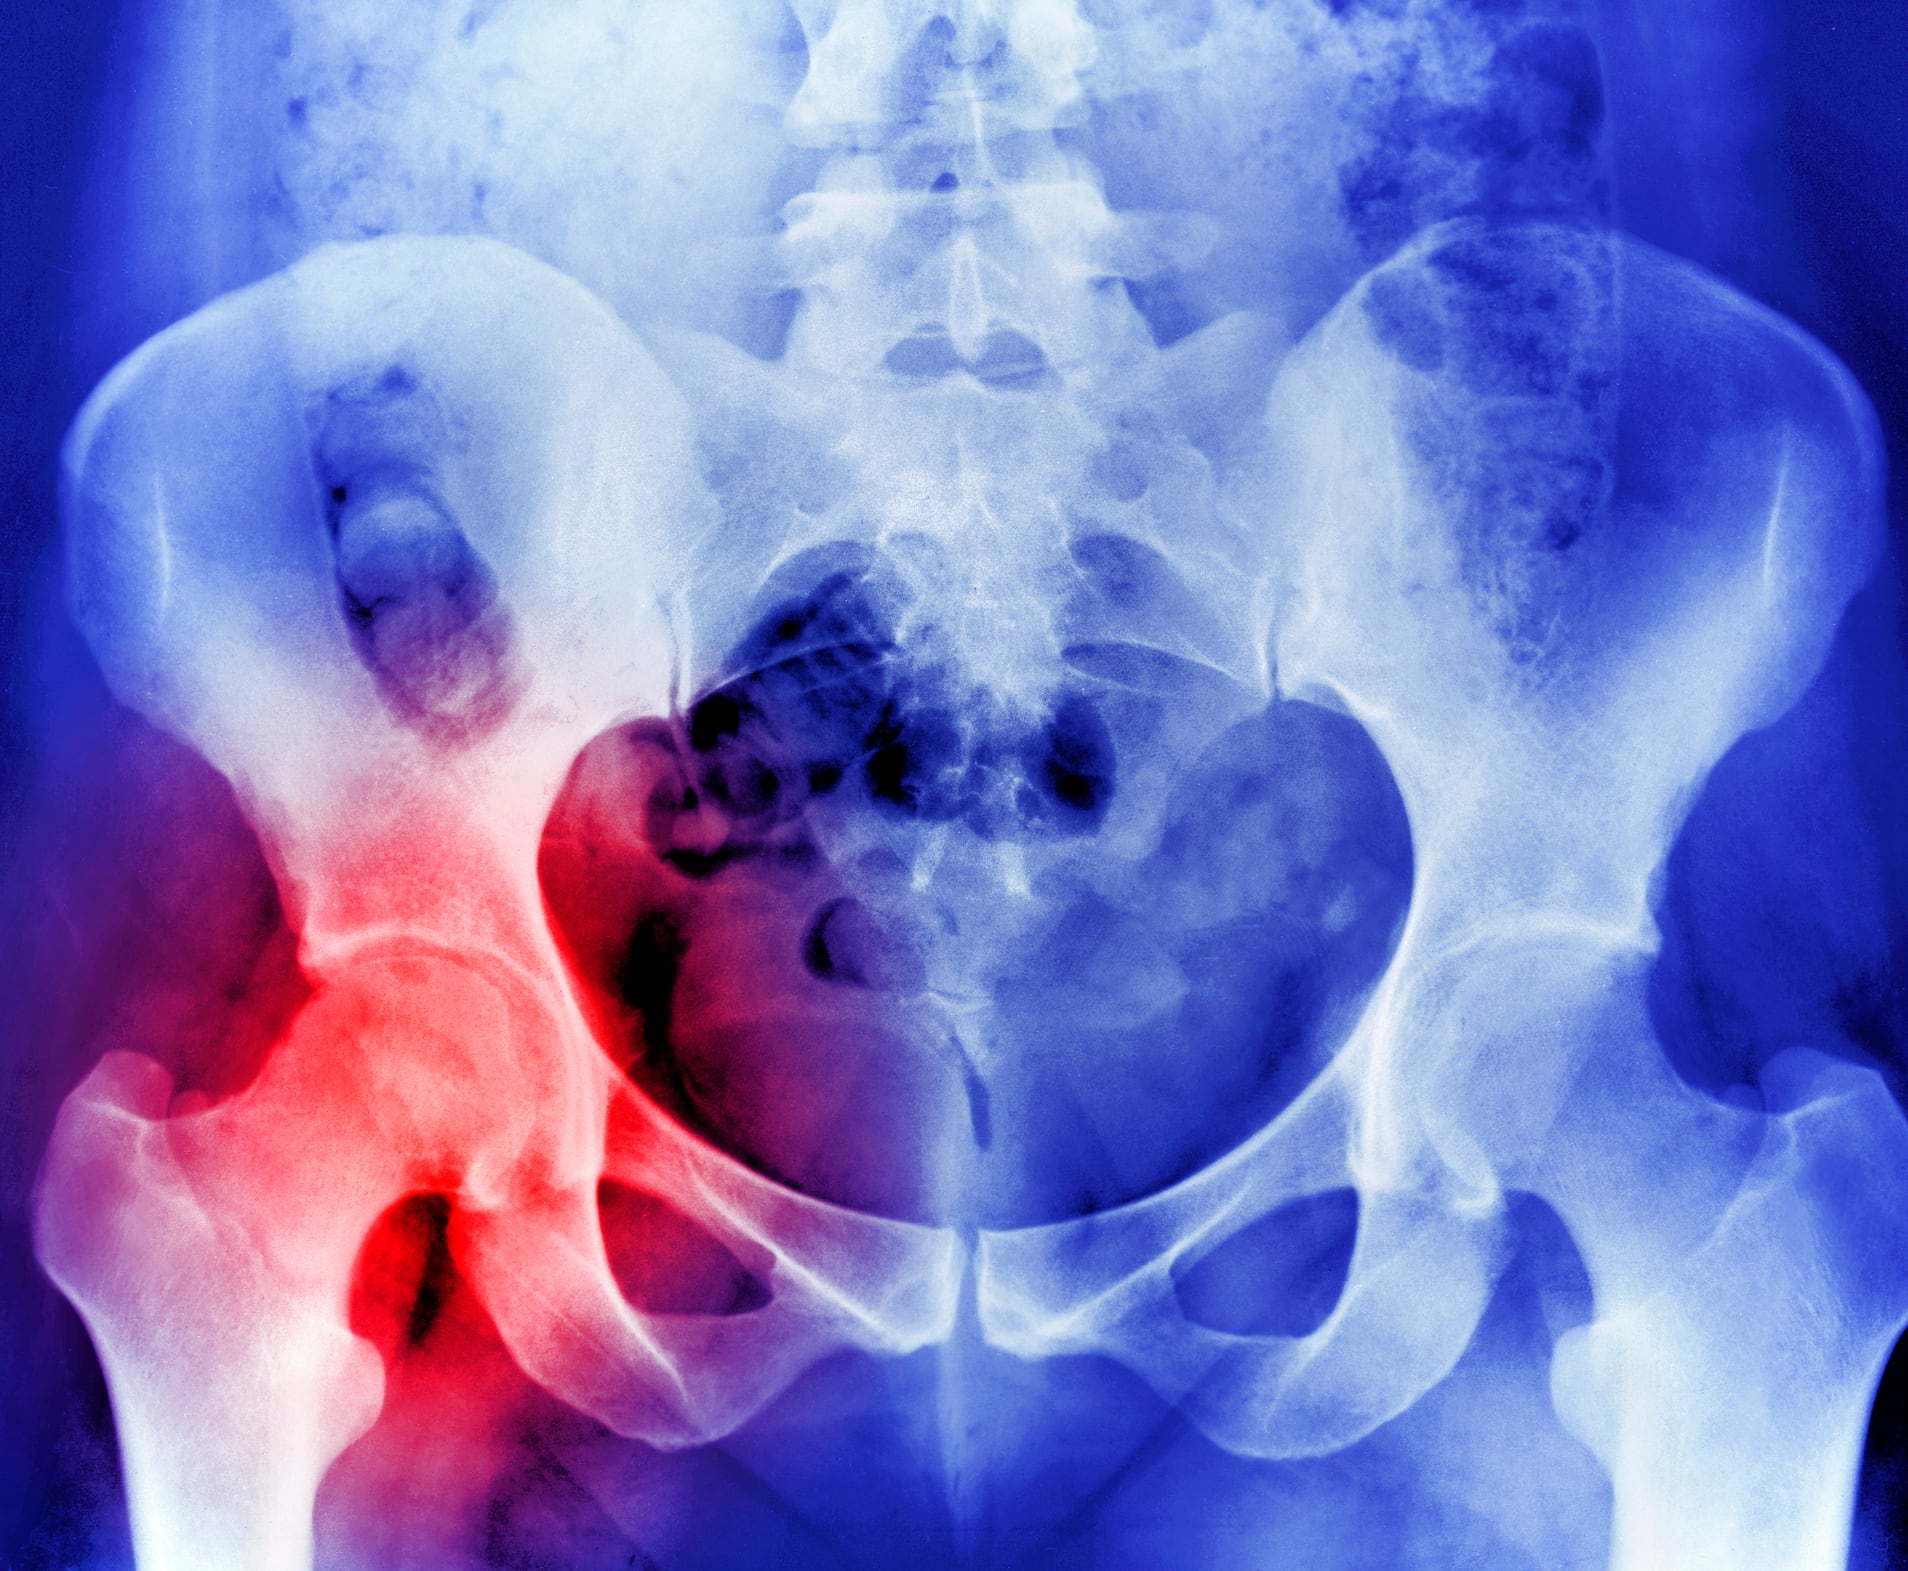

Una de las características de este padecimiento es que los huesos se vuelven más porosos, aumentado el número y la amplitud de las celdillas que existen en su interior. Se transforman a más delgados y frágiles, y como consecuencia, menos resistentes a los traumatismos, lo que hace que se fracturen con facilidad. Es una enfermedad que se presenta con mayor frecuencia en la muñeca, la cadera y las vértebras de la columna.